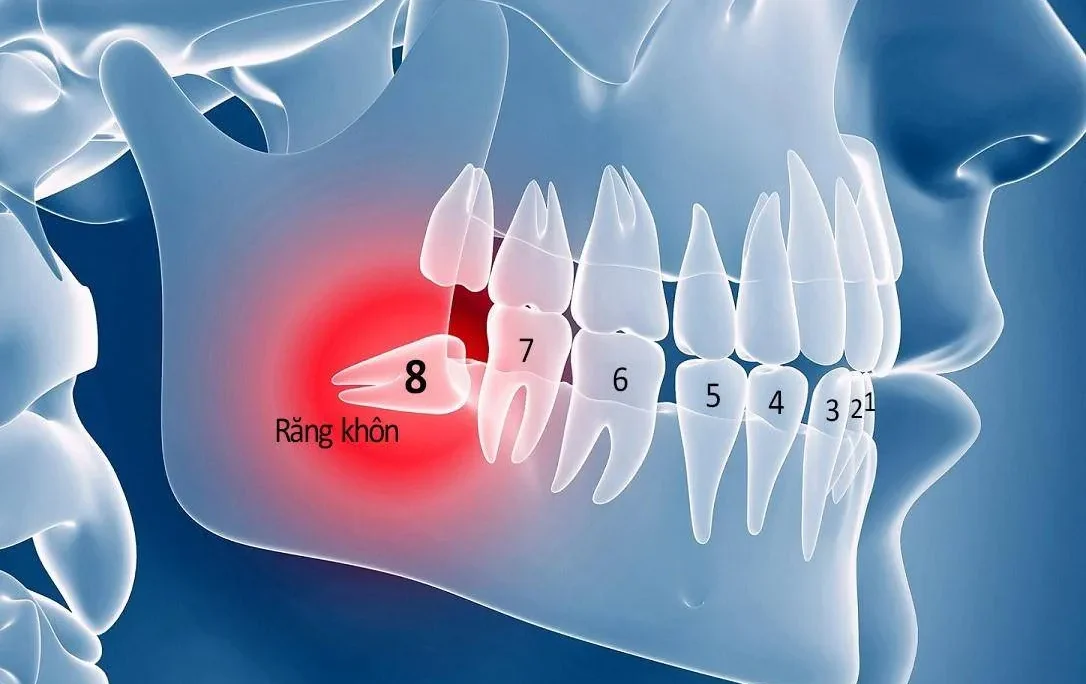

Răng cối là những chiếc răng lớn nhất trong hàm răng, mọc ở phía sau cùng, thường bắt đầu mọc từ khoảng 6 tuổi và tiếp tục mọc cho đến khi trưởng thành. Mỗi hàm thường có 6-8 chiếc răng cối (3 răng hàm lớn và 2-3 răng hàm nhỏ ở mỗi bên). Chúng đóng vai trò vô cùng quan trọng trong quá trình nghiền nát thức ăn, giúp tiêu hóa diễn ra thuận lợi.

- Răng cối mọc lệch, cản trở sự phát triển của các răng khác: Trong một số trường hợp, răng cối mọc ngầm hoặc mọc lệch có thể gây cản trở sự phát triển của các răng khác, ảnh hưởng đến khớp cắn và chức năng ăn nhai.